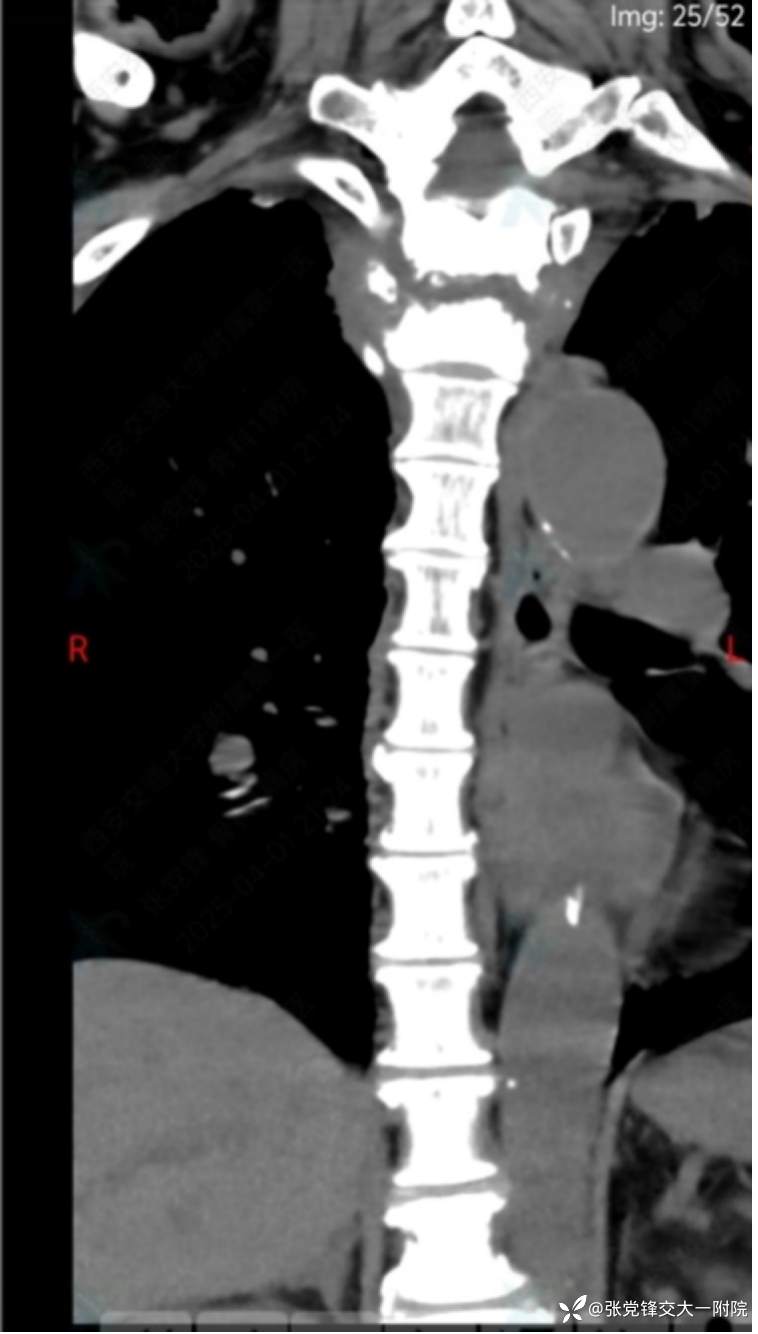

【影像学检查】

术前CT

全身骨显像:胸2-3椎体骨代谢增高,结合病史考虑脊柱结核可能。